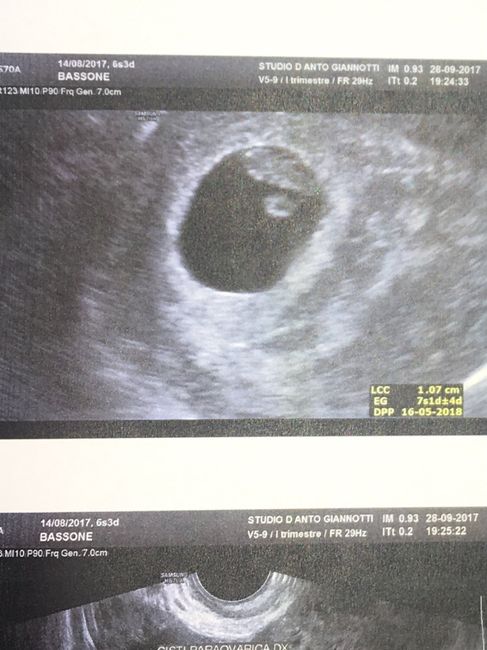

Salve a tutte ieri prima eco sono di 6 settimane anche se il gine mi ha dett sono di 10 giorni indietro ma facend i conti io mi trovo bene ho sentito battito e il cuore che pulsava forte...e dal eco essendo di 6 nn lp vedo piccolo ce chi nn riesce nemmeno a vederlo che dite? Come erano le vostre eco di 6 settimane?

Visto che misura un cm sarai incinta da 7 sett più o meno, sicuramente no d 8/9(sarebbe più grande) Cmq nn t basare sulla vista(grafica) un ecografo nn è come un altro...e poi cmq dalla tua eco a me sembra d vedere il sacco vitellino(a forma di disco) il tuo piccolino è il fagiolino attaccato lì.cmq nn t fissare l'importante è che il bimbo/a stia bene . Smiley heart

Ciao Michela quando sono andata al pronto soccorso misurava 3.9 mm mentre venerdì il gine nn me la detto ma sul foglio ce scritto CRL 1 cm nn so se sia la sua misura ma cmq ha detto che è di 6 settimane ma io lo vedo grande per essere di 6 e anche x me misura giusto nn sono indietro

Eccola a 6+3 era di 1 cm ma disse ke si portava di 4/5 gg più grande e anke noi sentimmo il suo cuoricino 😍💕

Prima ecografia 2